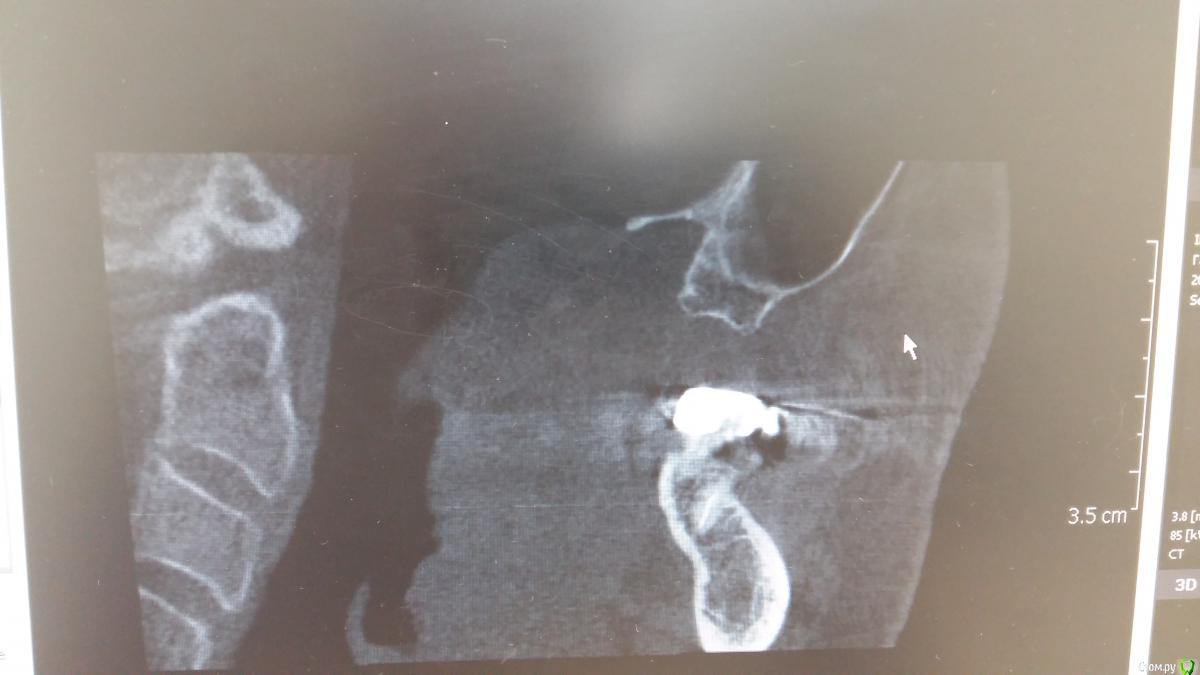

Zubnik7 Опубликовано 30 сентября, 2016 Автор Поделиться Опубликовано 30 сентября, 2016 Перегородка не полная,сейчас выложу новые срезы,более информативные Ссылка на комментарий

Zubnik7 Опубликовано 30 сентября, 2016 Автор Поделиться Опубликовано 30 сентября, 2016 Новые срезы Ссылка на комментарий